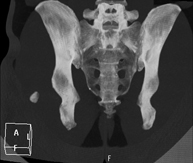

- Pelvic bone CT

Radiological examination based on an X-ray system and detectors that rotate around the patient, reconstructing the images by computer (multidetector computed tomography - MDCT) to study the bones, muscles and joints of the pelvis.

- Hip CT

Radiological examination based on an X-ray system and detectors that rotate around the patient, reconstructing the images by computer (multidetector computed tomography - MDCT) to study the bones, muscles and joints of the hips.